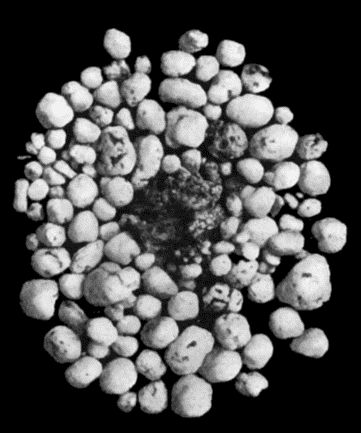

| 169. | Multiple Cartilaginous Loose Bodies from Knee-joint | 543 |